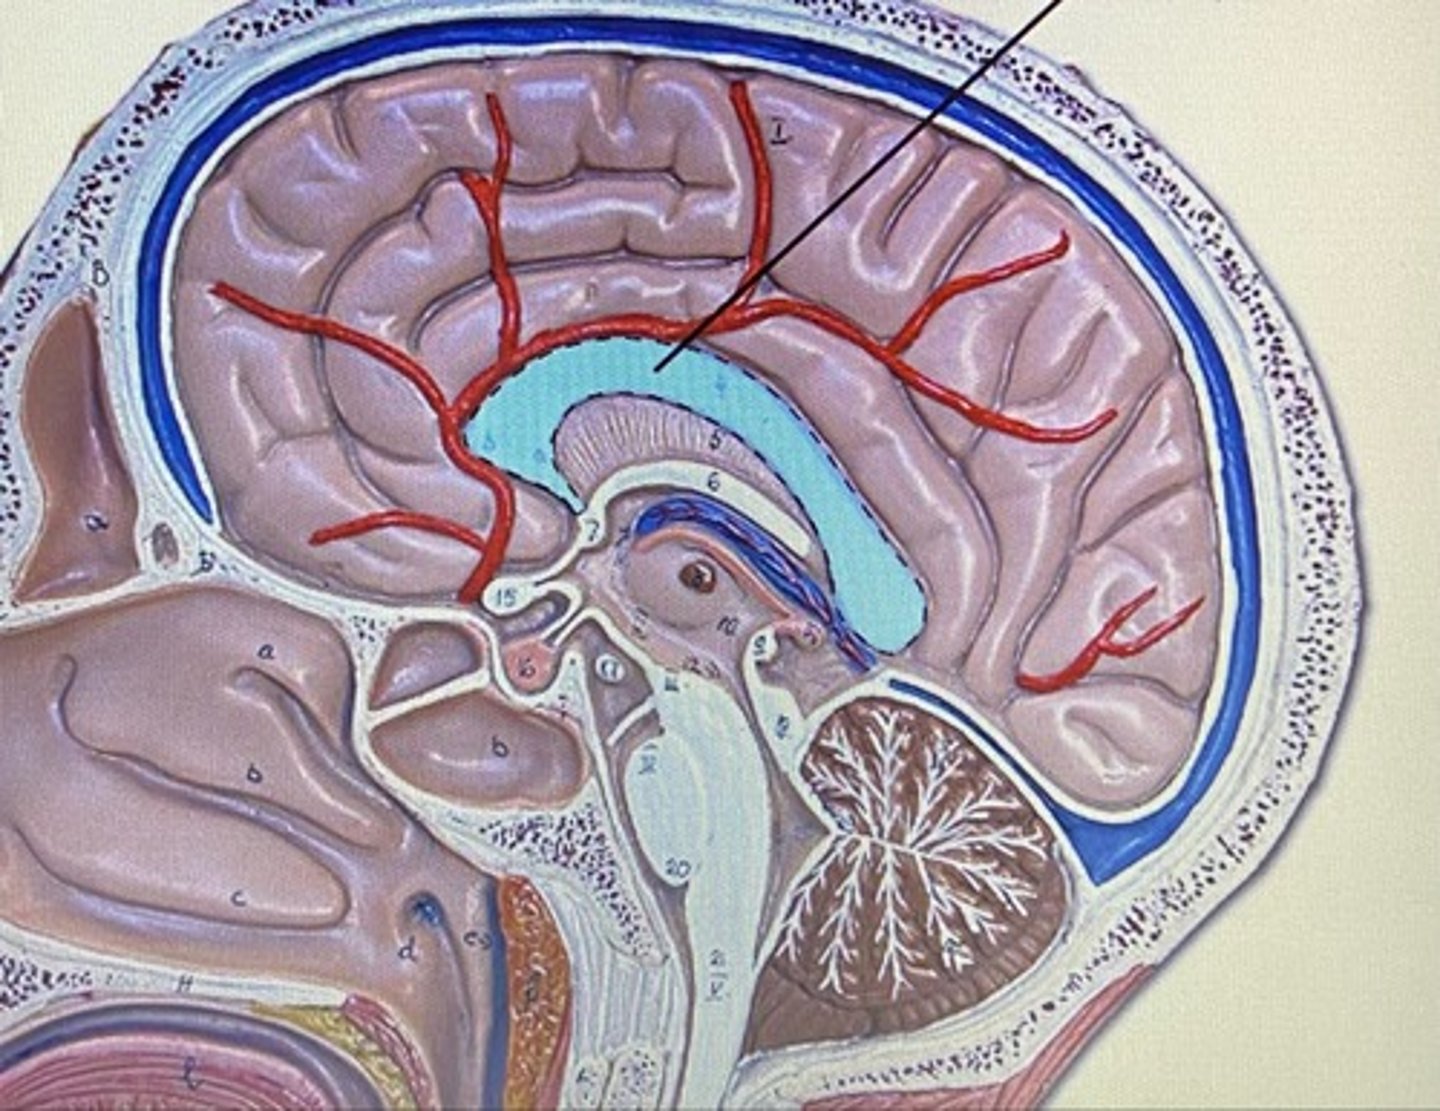

Meninges

The three protective membranes

-dura mater

-pia mater

-arachnoid

Dura Mater

Arachnoid Mater

Pia Mater

Lateral Ventricle

Third Ventricle